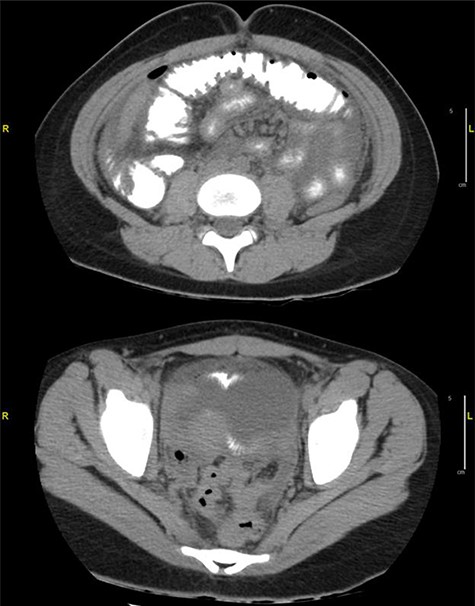

Case 1: A 14-year-old boy with a 2-day history of mild abdominal pain presented to the emergency department (ED) within 6 hours of sudden-onset severe abdominal pain, persistent, mostly in the periumbilical area. He denied nausea, vomiting, diarrhea, fever, melena and hematochezia. Past medical history only significant for ADHD on Adderall. On exam, he appeared in severe distress, with normal vital signs, diffuse abdominal rebound tenderness and rigidity. Laboratories revealed elevated white blood cell count (WBC) of 14.900/L and normal C-reactive protein. Abdominal ultrasound was unremarkable, but since the concern for acute abdomen, a computer tomography (CT) of the abdomen and pelvis was obtained, demonstrating a large pneumoperitoneum predominantly in the upper abdomen suggestive of perforated viscus (Fig. 1).

(a) CT abdomen and pelvis axial view. (b) CT abdomen and pelvis coronal view: there is a large pneumoperitoneum predominantly in the upper abdomen.